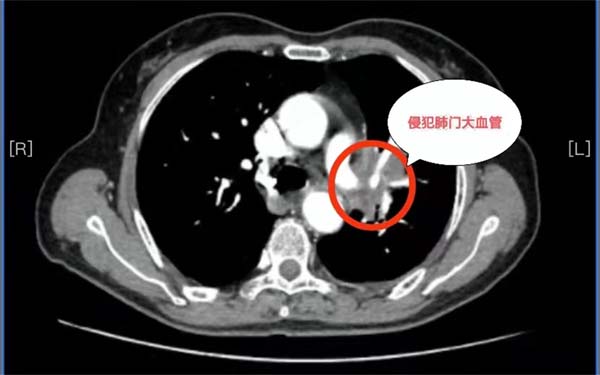

69岁的杨女士在当地医院不幸确诊为局部晚期肺癌,胸部CT检查发现左肺巨大肿瘤,已经侵犯到左肺门、左肺动脉干根部、纵隔及胸壁。当地医院建议杨女士到北京的大医院治疗。此时,患者一家陷入了极度的恐惧与绝望之中。

历经波折后求医无果,经多方打探,抱着最后一线希望杨女士和家人来到应急总医院胸外科求诊。胸外科副主任杨龙海博士从事胸外科专业多年,在肺癌方面具有丰富的诊治经验。杨龙海博士凭借丰富的临床经验,结合外院检查结果,排除远处转移,判断患者有手术的机会,且肺癌根治性手术远期效果相对较好,有治愈的可能。然而,肿瘤发现时已局部晚期,肿块巨大,侵犯到了左肺门大血管,侵犯纵隔及胸壁,加上患者伴有20多年的支气管扩张病史,致使患者症状较重,活动后气喘。这些因素导致手术需要切除整个左肺,手术难度及风险极高,切除过程会遇到肿瘤与肺门、纵隔、心包、胸膜等分离困难的难题,如果处理不当,可能出现大出血、循环呼吸衰竭等严重情况,随时危及生命。